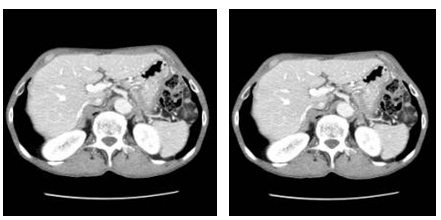

전산화단층촬영(CT)은 X-선을 우리 몸에 투과 시킨 후 얻어진 신호를 컴퓨터로 계산하여 신체의 단면을 영상으로 나타내는 검사입니다. 식도암에서는 흉부 및 복부 전산화단층촬영(CT)을 시행함으로써 식도암의 위치와 주위 조직으로의 침범 여부, 흉강 및 복강 내 림프절 전이의 판정(수술 전 병기 결정), 흉강 및 복강내의 원격 전이(림프절이 아닌 신체기관에의 전이) 판정 등에 이용되며, 식도암 이외에 동반된 흉부 및 복부질환의 진단에도 도움이 되며, 수술 후의 합병증을 확인하거나 항암화학요법의 반응 정도를 확인하는 데에도 많이 쓰입니다.

식도암에서 흉부 및 복부 전산화 단층촬영 이미지

[식도암에서 흉부 및 복부 전산화 단층촬영]

식도암은 뼈로도 쉽게 전이가 됩니다. 전신 뼈 스캔은 식도암의 뼈 전이를 진단하기 위해 하는 검사입니다.